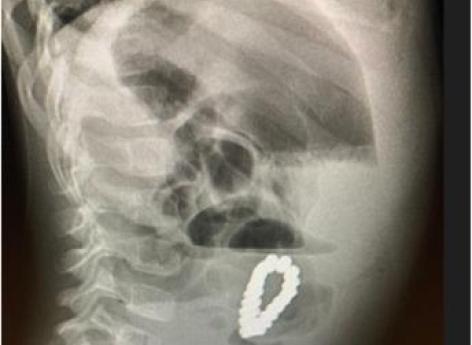

Les internes ont d'abord cru qu’il s’agissait d’une appendicite aiguë et ont donc décidé de lui enlever son appendice. Cependant, les douleurs au ventre et les vomissements se sont poursuivis les jours suivants l'intervention chirurgicale. Après avoir réalisé une radio abdominale, l'équipe a vite compris que le problème n’était pas l’appendice mais un amas de billes magnétiques logé dans la cavité abdominale. Les parents n’étaient pas au courant puisqu’ils n'ont pas vu leur enfant avaler ces éléments.

"Notre patient a ingéré 18 morceaux de billes magnétiques de forme hexagonale sur une durée inconnue mais en raison de leurs formes identiques, elles ont pu s'attirer et s'aligner les unes avec les autres pour former un amas provoquant une obstruction de l'intestin grêle", résument les médecins.

Très vite, ces derniers ont procédé à une laparotomie d'urgence. Cette opération consiste à ouvrir l'abdomen afin d'y prélever le bracelet constitué de 18 billes magnétiques de forme hexagonale qui s'étaient alignées. Durant l’intervention, les médecins ont aussi recousu les trous provoqués par le bracelet dans la paroi intestinale de l’enfant. Le petit patient a pu retourner chez lui six jours plus tard, sans séquelles comme a pu le confirmer le rendez-vous de suivi réalisé six mois après.